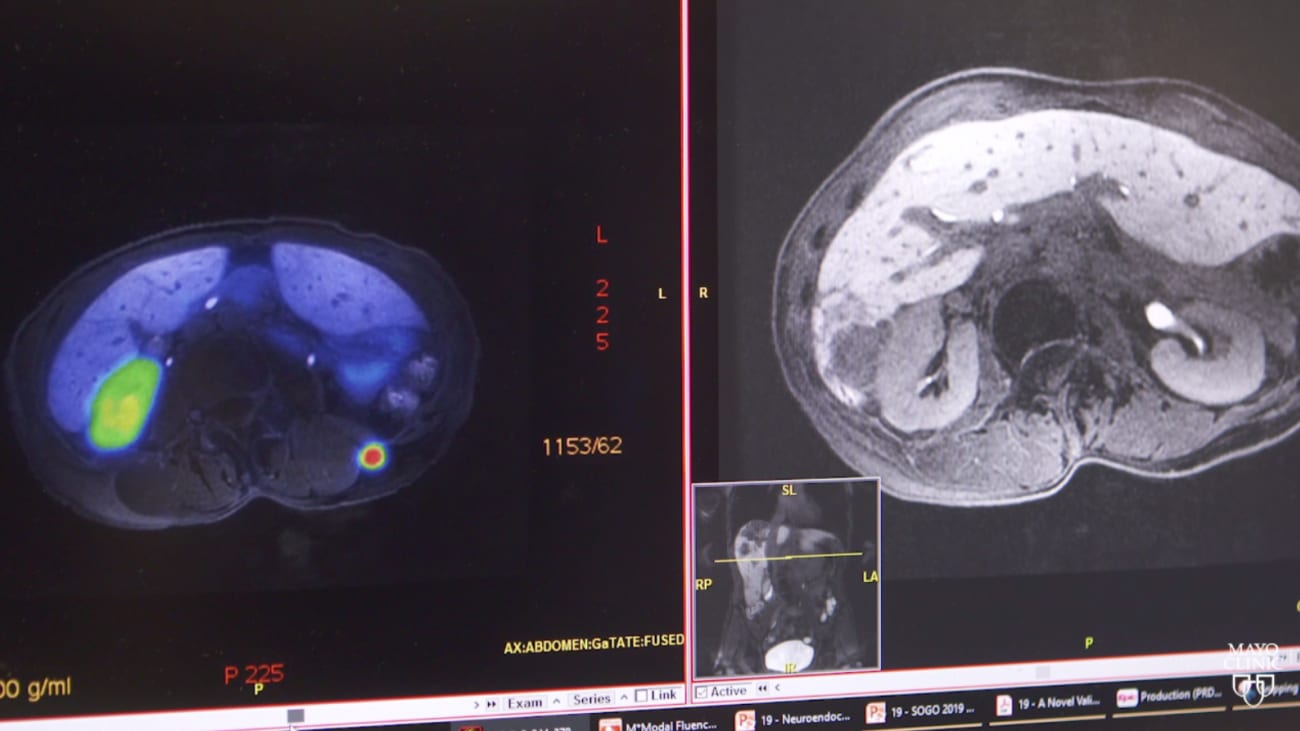

Mayo Clinic to lead new radiotracer trial for detecting pancreatic

Mayo Clinic to lead new radiotracer trial for detecting pancreatic Mayo Clinic Pancreatic Cancer Mayo clinic doctors are widely respected for their expertise in diagnosing and treating people with pancreatic cancer. New technologies are improving pancreatic cancer treatment, offering hope to patients facing one of the least survivable forms of cancer. How are breast cancer and pancreatic cancer connected? — recently made a discovery. The connection between breast cancer and pancreatic cancer is a.. Mayo Clinic Pancreatic Cancer.